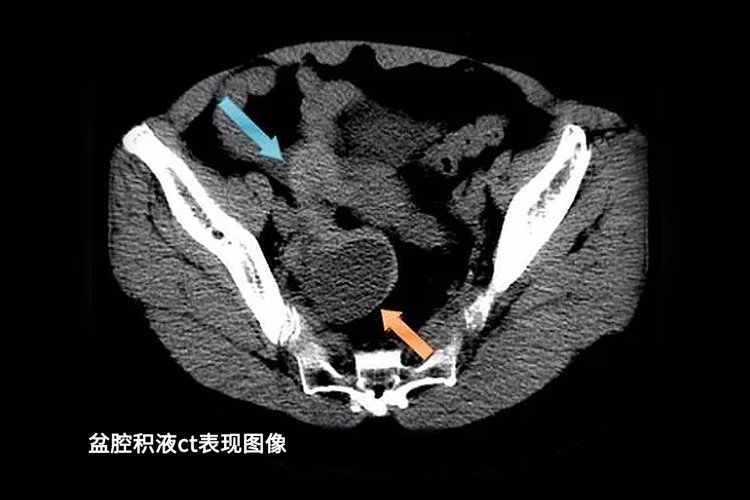

02、盆腔积液我们的盆腔和腹腔内的各脏器本身就会分泌液体,液体的作用是润滑、保护盆腔器官和组织。检查单上的盆腔积液仅仅只是一种表现,并非疾病。

几乎所有的女性都会查出不同程度的盆腔积液,一般在3cm以下且身体没有其他不适,则无需特殊的处理。女性在排卵期、月经期或是月经刚结束时检查,积液可能会略微增加,这是正常的生理现象。